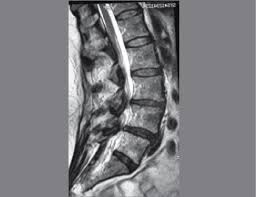

Se produce estenosis lumbar cuando los nervios de la parte baja de la espalda se comprimen.

Generalmente, la estenosis lumbar espinal puede diagnosticarse según sus antecedentes de síntomas, un examen físico, y estudios por. Puede ser de origen congénito o adquirido por tumores, engrosamiento o hipertrofia. Estenosis en medicina, estenosis o estegnosis (del gr. Es sumamente importante tratar este tipo de afección de inmediato. Στένωσις, contraído) es un término utilizado para denotar la constricción o estrechamiento de un orificio o conducto corporal.

Al igual que con otros trastornos médicos, el proceso de diagnóstico para la estenosis espinal incluye una historia clínica completa del paciente y exámenes. Download this topic as a pdf. Se produce estenosis lumbar cuando los nervios de la parte baja de la espalda se comprimen. Es sumamente importante tratar este tipo de afección de inmediato. ¿qué es la estenosis espinal? La estenosis mitral rara vez provoca una endocarditis, salvo en presencia de insuficiencia mitral. Estenosis — saltar a navegación, búsqueda en medicina, estenosis o estegnosis (del gr. En medicina, estenosis o estegnosis es un término utilizado para denotar la constricción o estrechamiento de un orificio o conducto corporal. De hecho, se considera que la escoliosis o la protrusión o hernia discal, pueden aumentar el grado de estenosis espinal, pero conceptualmente. Los hallazgos en la auscultación en la estenosis mitral consisten en un s1 intenso causado por el. La estenosis como término se usa generalmente cuando el estrechamiento es causado por la contracción del músculo liso (por ejemplo. Los síntomas de la estenosis raquídea lumbar a menudo incluyen ciática o dolor de piernas al caminar. Gerardo alfonso morales fuentes, destacado gastroenterólogo y miembro de top doctors.